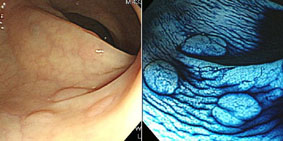

窄頻色帶攝影(narrow band imaging)技術利用血紅素會吸收特定波長可見光的原理,將內視鏡攝影畫面轉換成黏膜最淺層微血管的分佈畫面,再配合放大內視鏡(magnifying endoscopy)高達80倍以上放大如衛星照片般的精密內視鏡圖像,即可當場細查病變表面的微血管;早期腫瘤常在尚未造成組織變色、變形之前就出現表面微血管的變化,只要看得到這樣的變化,就可以不必等待切片結果,於活體內直接判讀病變的性質、範圍、嚴重程度。精密內視鏡的圖像對解析度要求特別高,本中心內視鏡室採用最頂級的日本製Olympus超高解像度攝影系統(HDTV),搭配專用的胃鏡(GIF-H260Z)及大腸鏡(CF-H260AZI),以做為各種影像強化技術的基礎設備。

最新的內視鏡科技:找出感覺不到的早期腫瘤(相關圖片)圖二. 左圖正中央發現一顆微小的大腸息肉,但無法確認它的性質;右圖可見窄頻色帶攝影配合放大內視鏡,根據微血管紋路及粗細判斷為表淺的良性腫瘤。